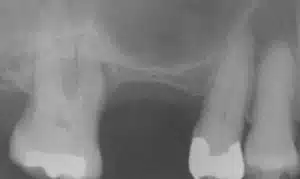

The dark space at the top of the photo is the sinus. The remaining bone is the thin white line between the teeth.

In this view sinus augmentation has been performed. The oval white structure is the bone graft material.